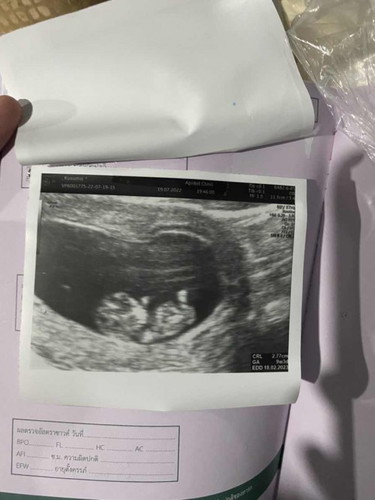

9week 3b ❤️❤️❤️

อันแรก9week3b. อันที่2. 8week3b ตัวโตเร็วมาก ลูกแม่ ยิ้มกริ่มตลอดเลยตอนหมดอัลตราซาวด์ ☺️☺️ ขอดูเจ้าตัวน้อยของแม่ๆตอน9weekหน่อยค่ะ #ท้องแรกคะ

ซาวด์ตอน9 6wks. ตอนนี้น้อง 12wks.แล้วค่ะ รอหมอนัดอีกทีเดือนหน้าค่ะ😍

ใช่ค่ะ หัวใจน้องเต้นแล้ว คนเป็นแม่ ตื่นเต้นตลอด ☺️☺️